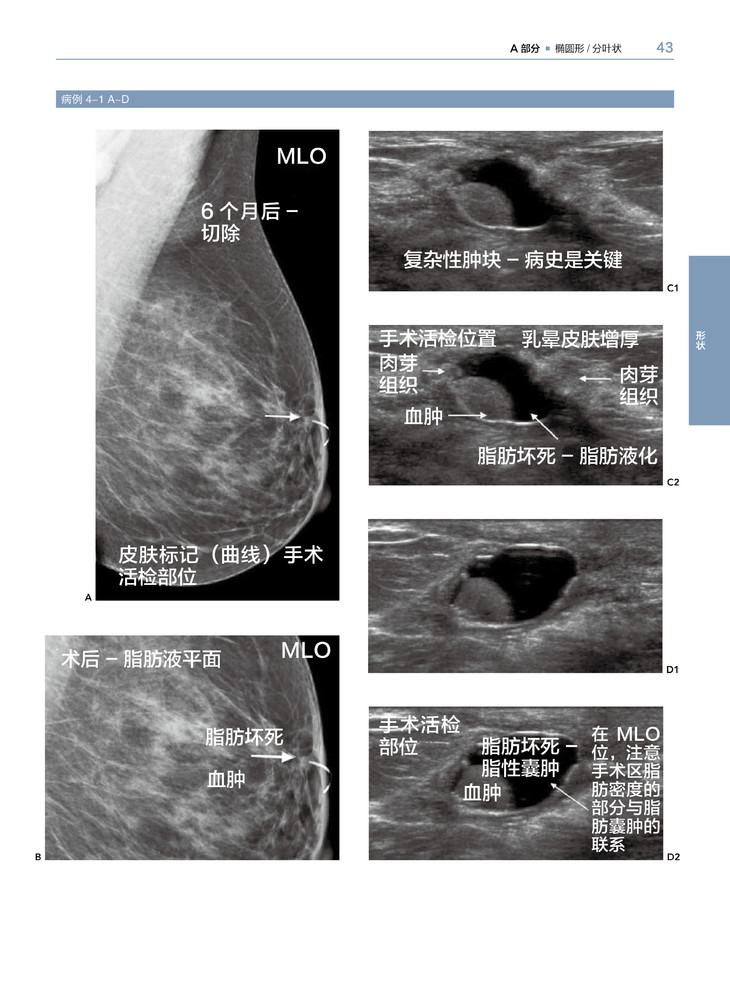

1.这本图集通过乳腺X线摄影或超声图像解释了乳腺影像 “怎样形成”和“为什么形成”的问题。应用病例优先选择的模式与你讲述了大量的常见和不常见的影像图像,与病理相结合阐述结果,帮助读者建立分析病例的能力,这样可以在诊断乳腺病例时信心十足。

2.对病例认识能力的提高,有赖于对病理描述分类的识别(例如肿块、钙化、结构扭曲等等及不太常见的恶性特征),而不是最后的病理诊断。

3.学习应用形状和边界去评估肿块,应用形态和分布去评估钙化,从重叠组织中辨别结构扭曲。领会如何应用大部分特征鉴别良性与恶性的可能性。

乳腺X线摄影和超声影像是乳腺影像检查最常用的两种方法。本书针对临床经常出现的有关乳腺癌影像表现,进行全面分析、归纳。乳腺癌主要是以三种形式表现的:肿块、钙化和结构变形。这本书主要分成以上3个主要部分,第四部分主要包括一些与恶性乳腺癌相关的重要影像表现。全书以病例为主,一共有400多个病例,文字简练,图片清晰,有病例的影像检查图,病理图,代表性强,能为各级影像科、乳腺科医生提供宝贵的参考价值。